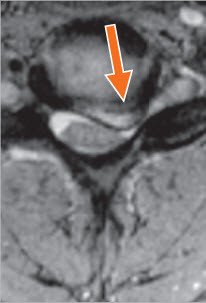

Die Bandscheiben sind flüssigkeitshaltige Kissen aus zähem und elastischem Bindegewebe. Sie verbinden je zwei Wirbelkörper miteinander und ermöglichen die Bewegung der Wirbelsäule. Eine besondere Form des Bandscheibenverschleisses ist die Diskushernie (Bandscheibenvorfall). Wenn die Bandscheibe nicht mehr ausreichend widerstandsfähig ist, wölbt sich ihre Fläche, und es kommt zu einer Bandscheibenprotrusion (Vorwölbung), oder ein Stück der Bandscheibe löst sich von der Bandscheibenmasse und drängt sich aus dem Raum zwischen den Wirbelkörpern in den Nervenkanal heraus (Bandscheiben-Hernie).

Der Vorfall einer Bandscheibe an der Halswirbelsäule kann eine der Nervenwurzeln einklemmen, die Arm und Hand versorgen. Der Patient hat oft Schmerzen im Genick, die stärker werden, wenn er den Kopf bewegt, sowie Schmerzen, Gefühlsstörungen und Schwäche in einem Arm und in einer Hand. Schwäche und Gefühlsstörungen können besonders in der Gebrauchshand behindernd sein. Nur selten kann ein grosser Bandscheibenvorfall dazu führen, dass das Rückenmark eingeklemmt wird, was Steifigkeit der Beine verursachen und dadurch zu Gehschwierigkeiten führen kann.

Die Schmerzen und das Kribbeln werden bei einer Nervenwurzeleinklemmung nicht im ganzen Arm und in der Hand empfunden, sondern spezifisch im Wirkungsgebiet des gereizten oder eingeklemmten Nervs (Abb. 1). Ist beispielsweise die sechste Nervenwurzel beeinträchtigt, wird der Schmerz bis in den Daumen empfunden und bei Beeinträchtigung der siebten Nervenwurzel aber im Zeige- und Mittelfinger.

Die Vorderfläche der Halswirbelsäule wird durch einen kleinen Hautschnitt entlang einer Hautfurche auf der rechten Seite des Halses freigelegt. Dieses Verfahren wird auch bei Beschwerden des linken Armes eingesetzt. Der Bandscheibenvorfall (Hernie), welcher die Nervenwurzel reizt und einklemmt, wird mit dem Mikroskop identifiziert und entfernt. In ausgewählten Fällen kann die Hernie (Bandscheibenvorfall) nur von hinten entfernt werden.